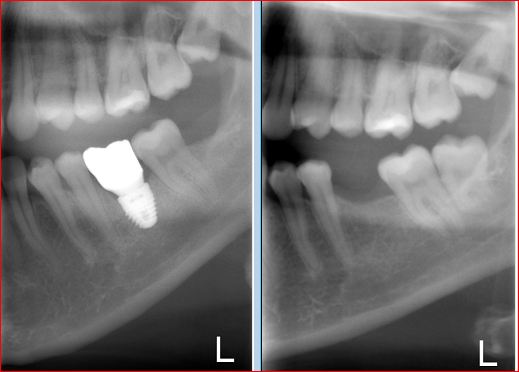

IMMEDIATE LOWER MOLAR REPLACEMENT

This type of cases Dr. Andrews encounters on a regular basis.

A 30 year old was concerned with the discomfort next to his impacted wisdom tooth and pain associated with cold and hot temperatures around the decayed back teeth.

After thorough dental examination Dr. Andrews recommended to extract the wisdom tooth (#17) and the second molar (#18) due to severe decay and poor prognosis for both teeth and to replace the second molar (#18) with a dental implant.

During only one 45-minute surgery both teeth were removed, a minor bone graft was placed and a wide-diameter (7 mm) dental implant was immediately inserted to replace the second molar. Four months later , #18 implant was restored with an all-ceramic crown.

Revolutionary digital scanning technology and CAD/CAM fabrication process had been used by Dr. Andrews to create an ideal emergence profile, ideal bite and natural anatomy for the crown.

Cavities on other teeth were treated with mercury-free, bio-mimetic white composite fillings.